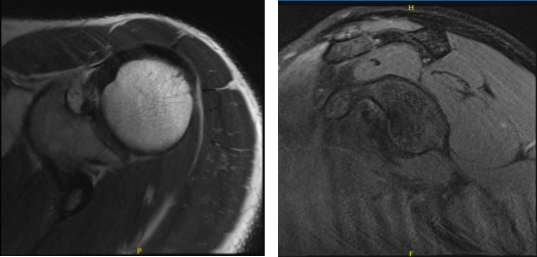

After three months, the patient returned to the office still complaining of bilateral shoulder pain. Advised the patient to undergo an MRI to see any improvement from the last visit. Right Shoulder MRI still showed Chronic AC joint sprain.

MRI – 3T Right Shoulder Non-contrast